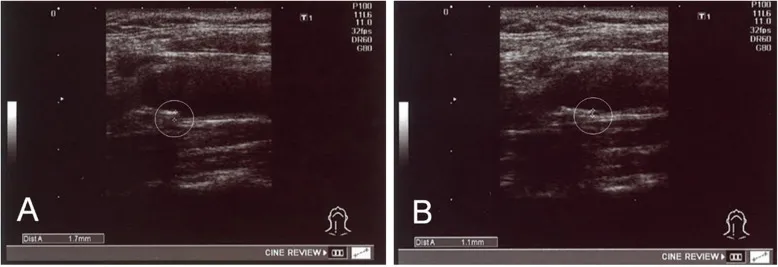

经过治疗,实验中一名患者内膜中膜厚度从1.7毫米降至1.1毫米